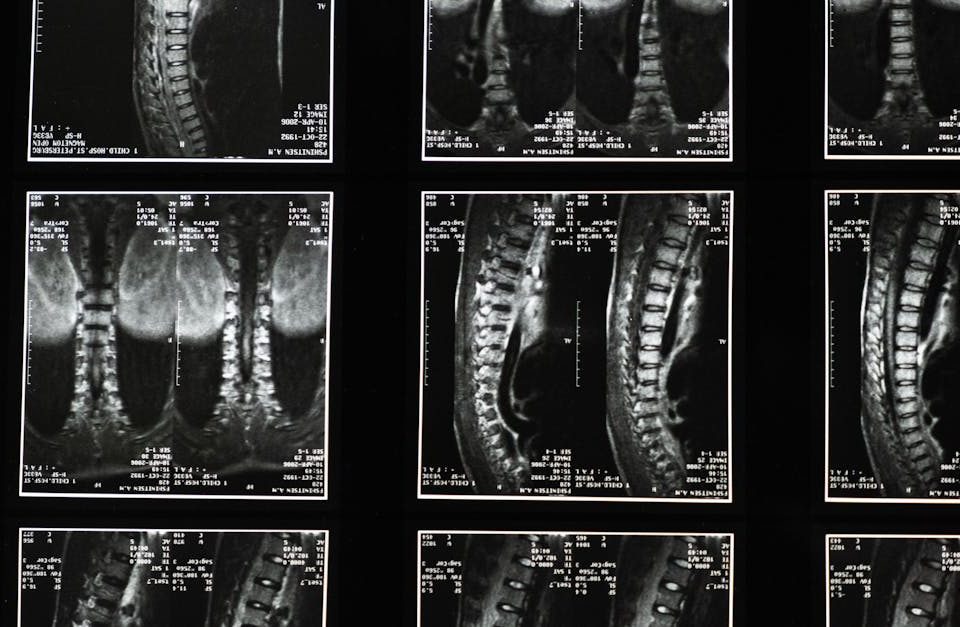

EN BREF Le diagnostic précis avant un traitement par décompression neurovertébrale consiste en une évaluation approfondie de l’état de santé du patient. À Montréal, cette approche […]